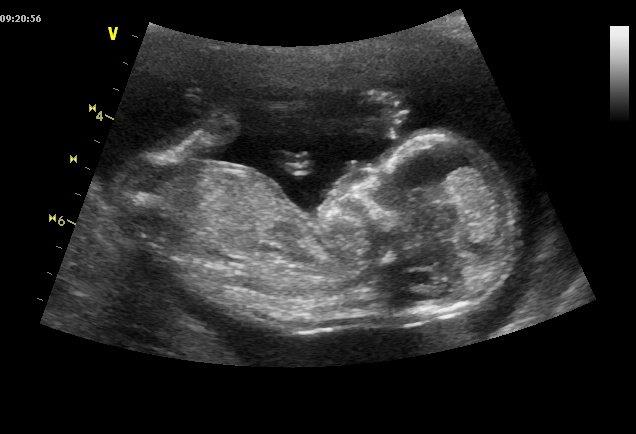

Tento týden jsem byla objednaná k panu doktorovi MUDr. Miroslavu Břešťákovi na prvotrimestrální screening. Po přečtení pár článků na internetu jsem nebyla úplně nejklidnější, protože to vypadalo jako nějaké ne moc příjemné vyšetření a testy. Opak byl však pravdou. Zpětně musím říci, že to bylo jedno z nejhezčích a nejemotivnějších vyšetření, které jsem doposud absolvovala. Pan doktor byl strašně milý, na mé všetečné dotazy trpělivě odpovídal a na konci vyšetření pro mě/nás měl tu nejlepší zprávu a to, že je mrňousek naprosto v pořádku. 🙂